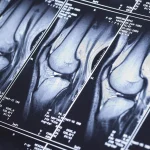

МРТ суглобів: точна діагностика травм, артриту та артрозу

Коли суглоби дають про себе знати больом, обмеженням рухливості або незрозумілим хрускотом, звичайного огляду лікаря часто буває недостатньо. Для постановки…